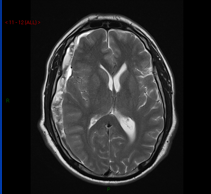

A 45 year old lady presenst to her GP with a headache. She says this has been going on for 6 weeks and is worse is the morning though she is particularly worried becauae she is now experiencing some visual loss. On further questioning she admits to being in a small car accident 7 weeks ago. This is her CT scan.

Subdural haematoma